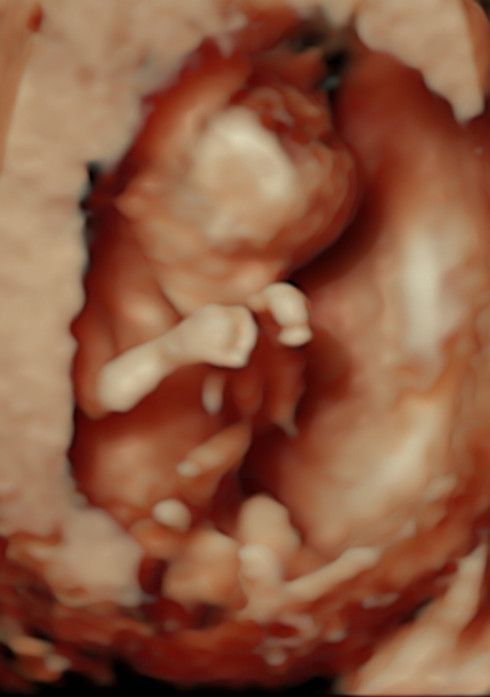

Mi occupo anche di GRAVIDANZA  a 360° accompagnandoti in tutto il percorso ed eseguendo ogni tipo di ecografia: ecografie ostetriche I trimestre, translucenza nucale, ecografia ostetrica morfologica, ecografia ostetrica 3D-4D ed ecografie III trimestre.